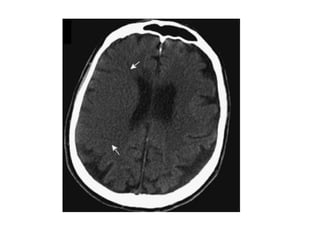

(Left) T2 and diffusion (Right) showing bilateral thalamic infarcts

NECT shows hyperdense internal veins and bilateral (R > L) thalami

hypodensities , compatible with dural vein thrombosis and venous

-Thrombosis of the deep cerebral veins may involve the

basal ganglia , thalami , midbrain and mesial temporal

lobes in a relatively symmetrical fashion